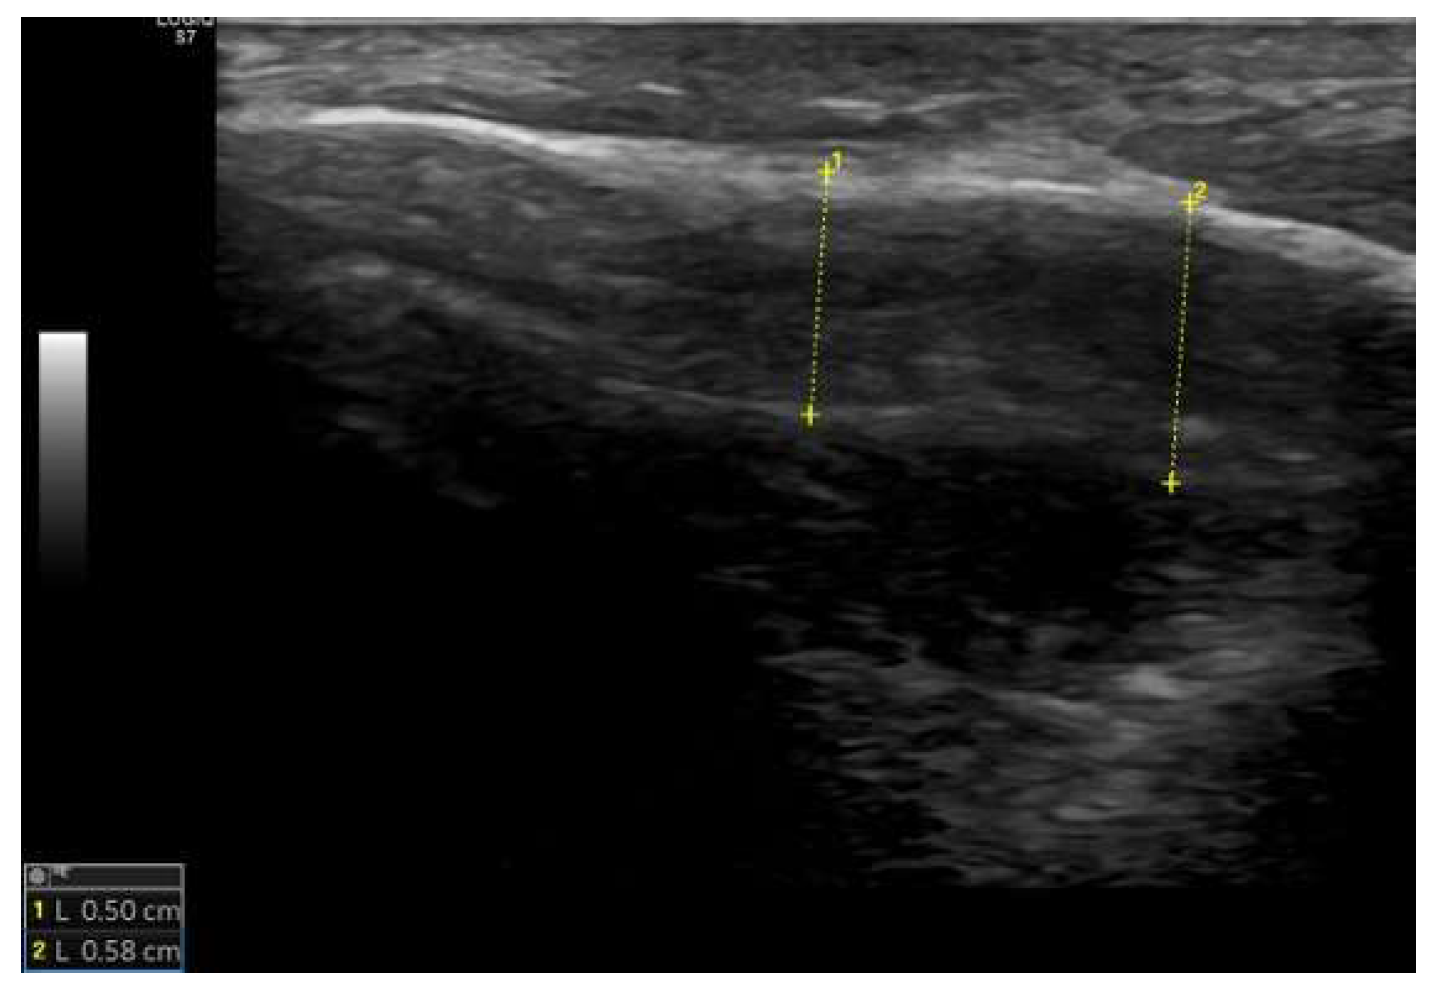

Ultrasound examination of the mastoid

| Group C | Group TM | U | p | ||

| Skin thickness (mm) | Median (IQR) | 3,73 (Q1: 3,6; Q3: 3,93) |

3,7 (Q1: 3,59; Q3: 3,89) |

477,0 | 0,929 |

| Min. | 3,0 | 3,3 | |||

| Max. | 4,7 | 4,3 | |||

| Cortical bone thickness (mm) | Median (IQR) | 5,71 (Q1: 5,2; Q3: 6,36) |

5,77 (Q1: 5,2; Q3: 6,42) |

444,0 | 0,976 |

| Min. | 4,13 | 1,93 | |||

| Max. | 7,97 | 7,97 | |||